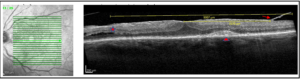

OCT macula scan revealed a thick hyper-reflective band with surface retinal wrinkling, confirming the presence of tractional ERM OU. OCT macula scan OD was stable in central macular thickness and appearance compared to previous scans. Of note with the OCT macula scan OS, an area of focal VMT appeared along the inferotemporal arcade. The nasal portion of the vitreoretinal traction appeared to break off just superior to the area of traction (Figure 1). A broad area of vitreoretinal traction temporal to the macula was pulling the temporal portion of the ERM. This portion of the ERM appeared to break off, along with the vitreoretinal traction, just inferior to the superotemporal arcade (Figure 2). In addition, central macular thickness had increased, and an area of retinoschisis arose temporal to the optic nerve, along with a new drusenoid pigment epithelial detachment (PED) temporal to the fovea (Figure 3). OCT angiography ruled out signs of choroidal neovascular membrane. These unexpected findings prompted a review of all previous OCT macula scans OS, which revealed that the areas of vitreoretinal traction had been present for the past 10 years and the breakage points were first observed 5 years ago. A significant increase in central macular thickness had begun 3 years prior to this visit, while the development of retinoschisis temporal to the optic nerve appeared 1 year prior to this visit.

![]() Figure 1. OCT macula scan OS in 2020 that prompted review of previous OCT scans. (a) An area of focal vitreoretinal traction (arrow) along the inferotemporal arcade. (b-d) The nasal portion of the vitreoretinal traction appears to break off (arrow) just superior to the area of traction. Click to enlarge |